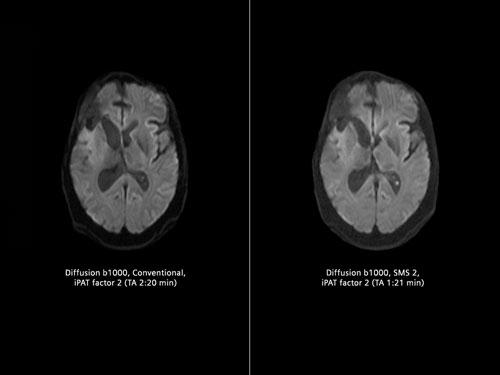

While new applications may be drawing a lot of attention, vendors are still rolling out enhancements related to brain scans as well. Siemens debuted two new applications at RSNA 2015 that can reduce brain scan times while enhancing image quality.

SMS (Simultaneous Multi-Slice) acquires multiple diffusion tensor imaging (DTI) slices simultaneously, an application that is particularly useful for surgical planning, according to Jan Chudzik, head of global product marketing, MR, for Siemens. “This is a paradigm shift because typically in the past we were acquiring those slices sequentially,” said Chudzik in the itnTV video. The largest benefit is that this reduces scan time significantly, a bonus for DTI patients and others who may have difficulty keeping still during the exam, including pediatrics. “This will have much greater potential even in the future because that can also be applied to other body regions,” Chudzik told Freiherr.